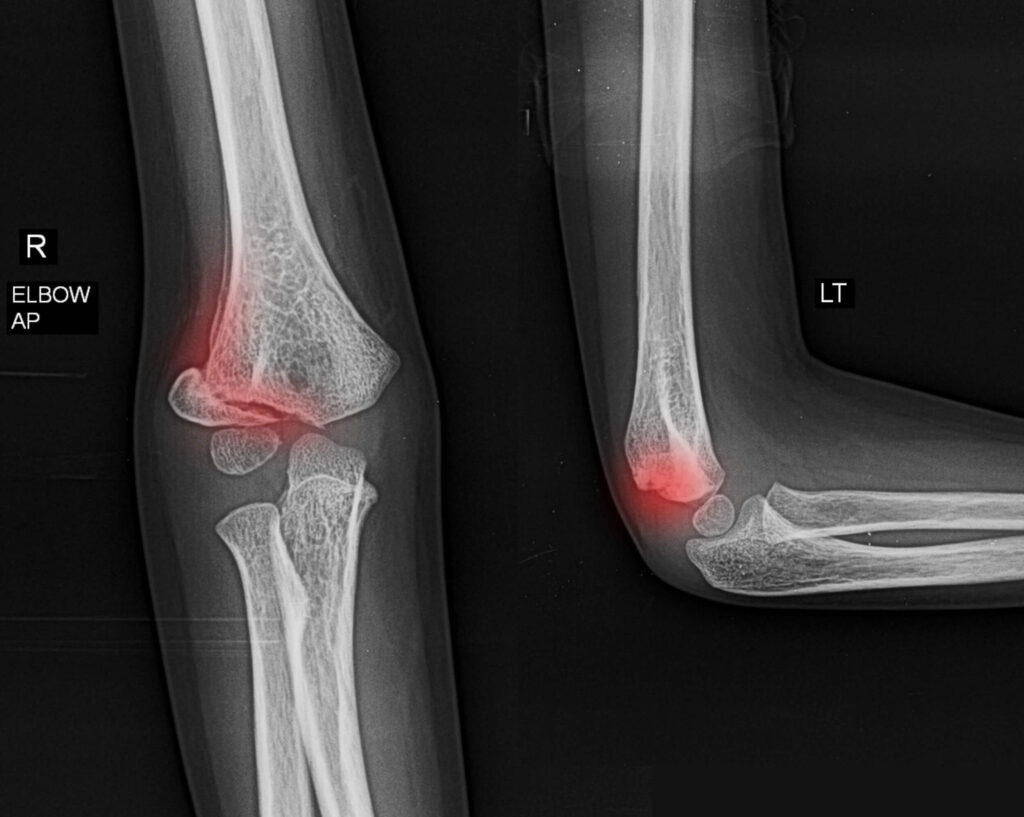

Fractures and Dislocations – Breaks or misalignment of elbow bones often caused by falls or accidents

Our skilled medical team offers thorough evaluations using on-site X-rays and ultrasound imaging to accurately diagnose elbow conditions. Personalized treatment plans include: